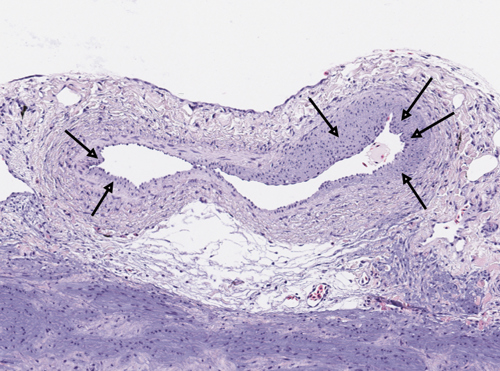

Arteriosklerose omfatter en gruppe tilstander med fortykket og forstivet arterievegg. Forandringene består av proliferasjon av glatt muskulatur og sees som «putedannelser» på innsiden av karveggen. Tilstanden forekommer hos både villaks og oppdrettslaks, men utbredelsen er ikke kjent. Pharmaq Analytiq startet med systematisk registrering av arteriosklerose midtveis i 2023, og vi er også involvert i forskningsprosjekter som skal undersøke forekomst, årsaksforhold og eventuelle sammenhenger med annen hjertepatologi. Arteriosklerose kan føre til nedsatt oksygentilførsel til den kompakte hjertemuskulaturen, og dermed disponere for stressrelatert dødelighet.

Bilde: Vevssnitt fra koronarkar fra laks i sjø. Bildet viser arteriosklerotiske forandringer i karveggen (piler).